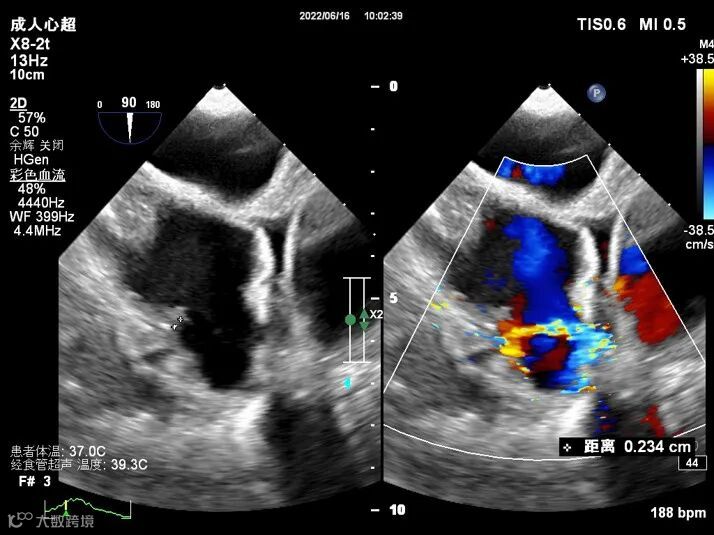

TEE图像如下:

图2:CDFI示左心耳内可见湍流血流信号

图6:显示回旋支与左心耳之间可见一瘘口,宽约0.2cm。